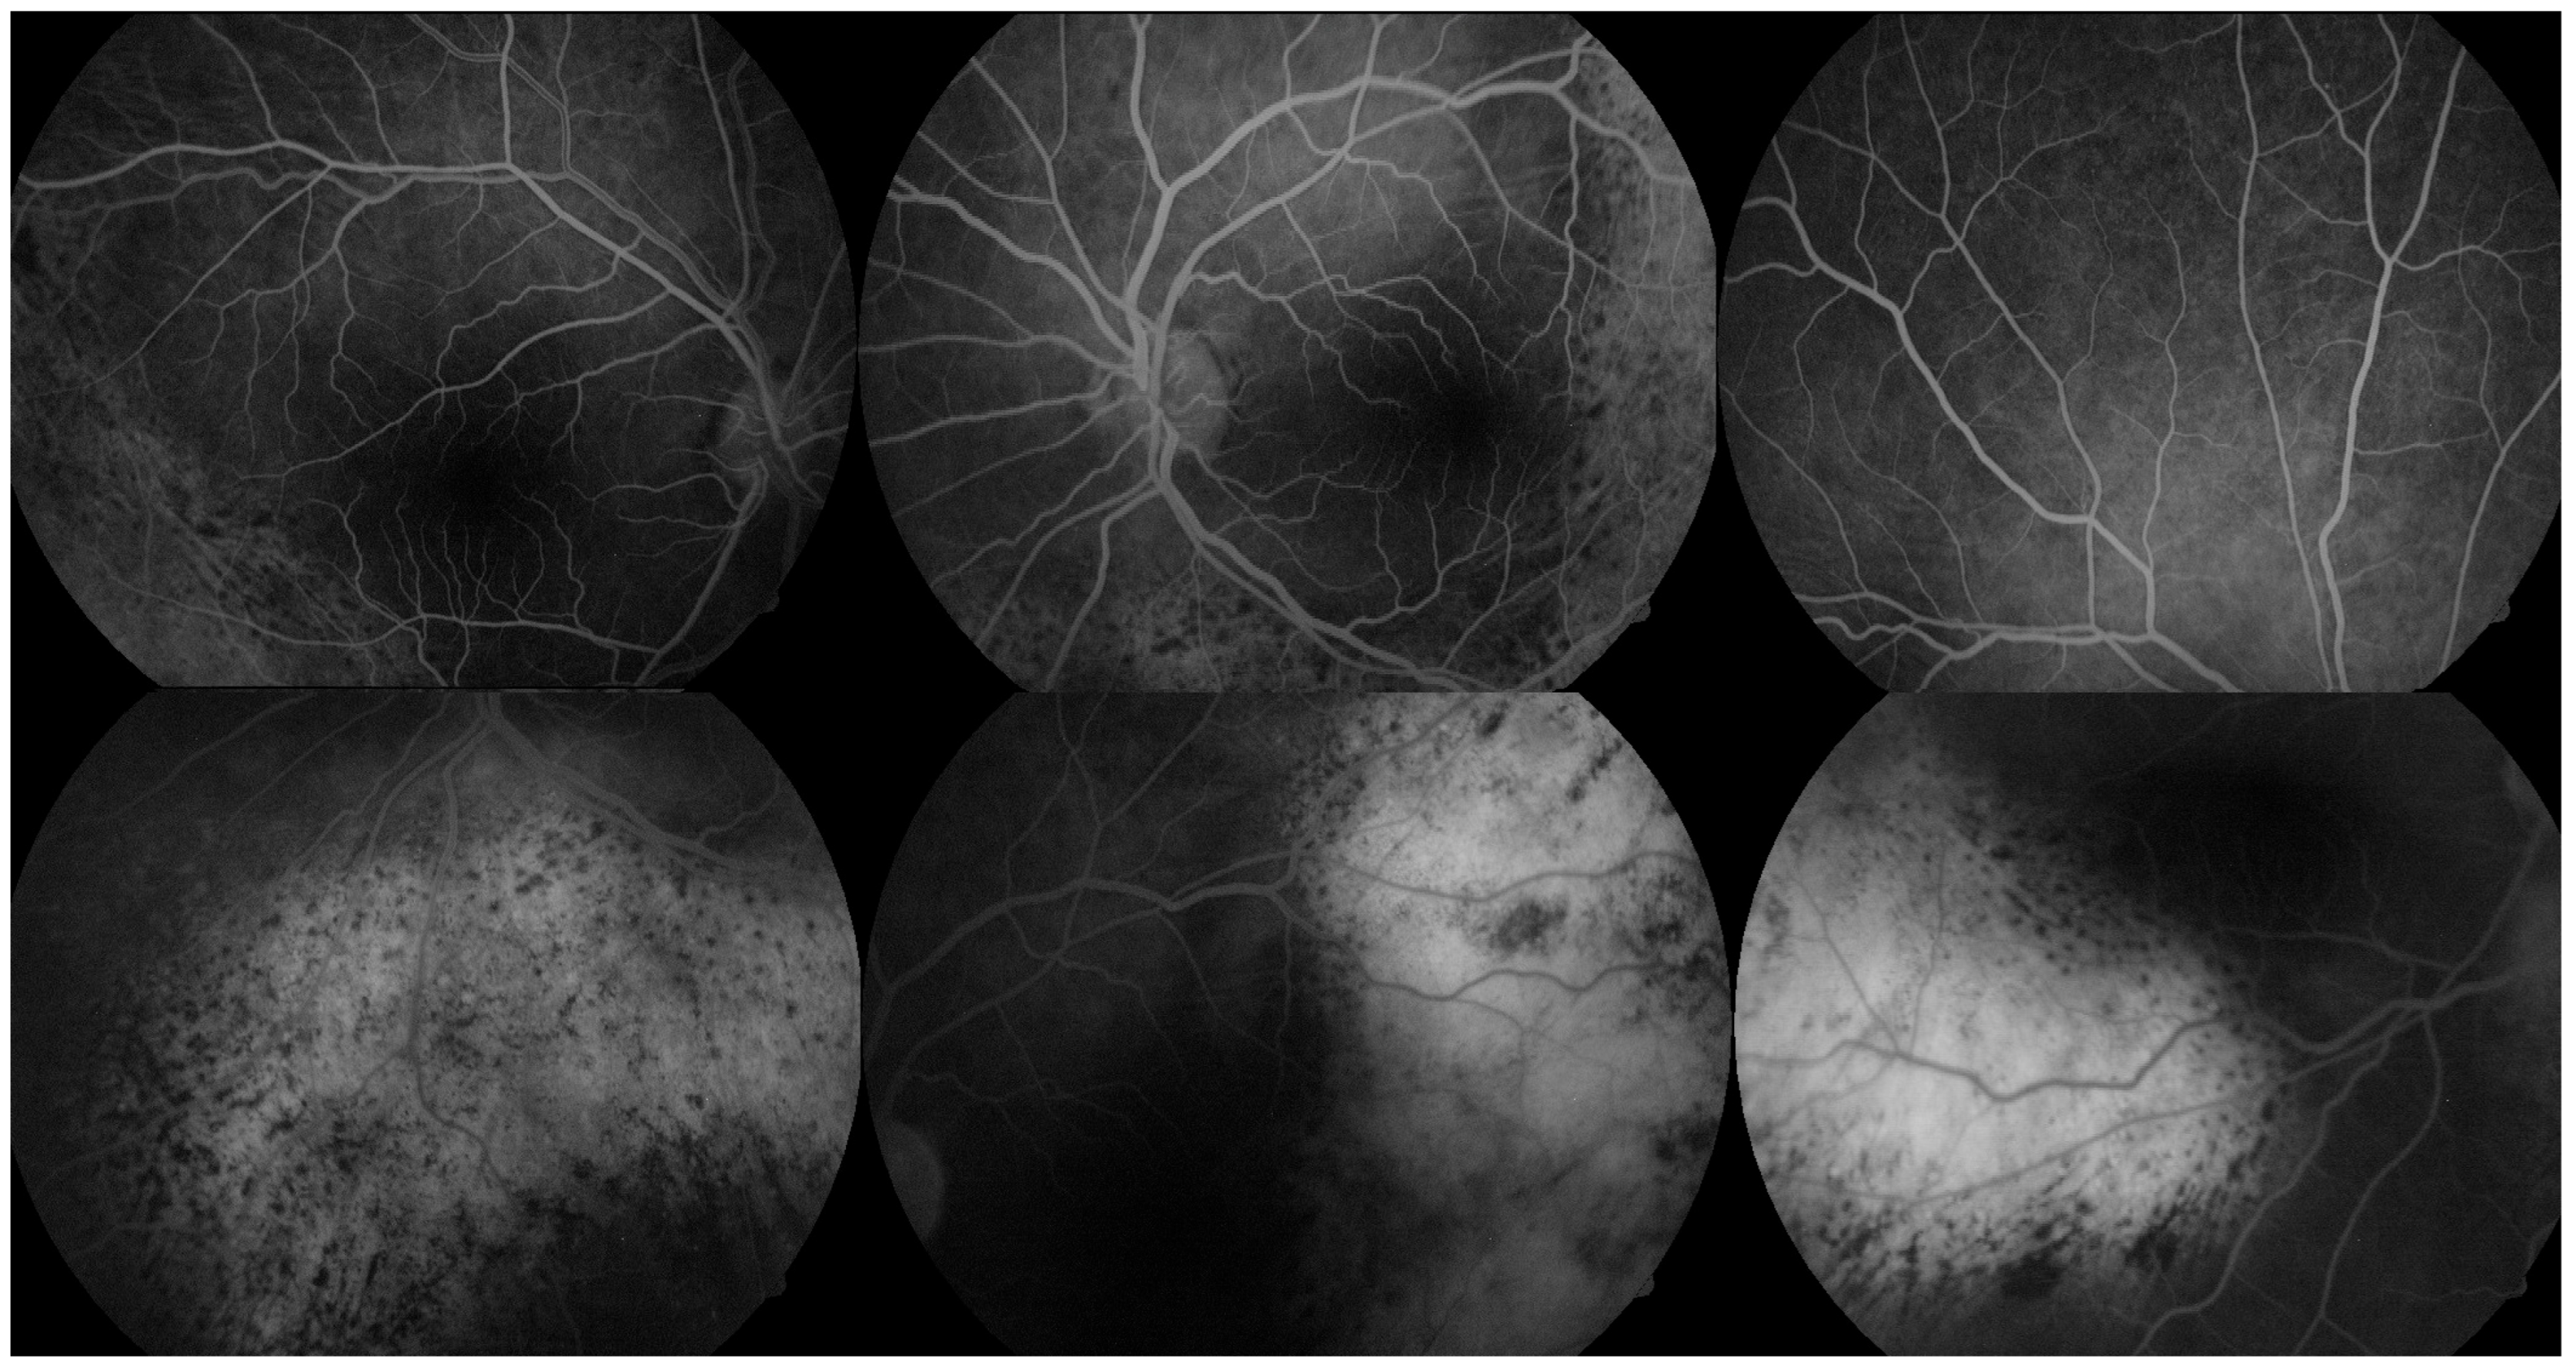

FA revealed multiple areas of early hyperfluorescence corresponding to the orange-red subretinal lesions, while the retinal vasculature remained largely preserved. In the late phase, persistent hyperfluorescence and focal dye pooling were noted, suggestive of RPE disruption and localized serous retinal detachment (Figure 2).

Figure 2. FA of both eyes illustrating vascular and RPE alterations suggestive of BDUMP. Top row (early-phase angiograms): Early-phase FA images show intact retinal vasculature with multiple areas of early hyperfluorescence corresponding to the orange-red subretinal lesions seen in fundus photographs. The hyperfluorescence is mottled and geographic, primarily involving the posterior pole and inferior retina. Bottom row (late-phase angiograms): Late-phase FA demonstrates persistent hyperfluorescence and focal pooling of dye in areas of RPE disturbance and shallow subretinal fluid. Scattered hypofluorescent zones may represent melanocytic proliferation or focal choroidal thickening, consistent with early BDUMP-related structural changes.